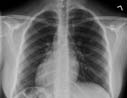

Posteroanterior chest on someone with pneumonia. The pneumonia is the white substance in the lower part of each lung.